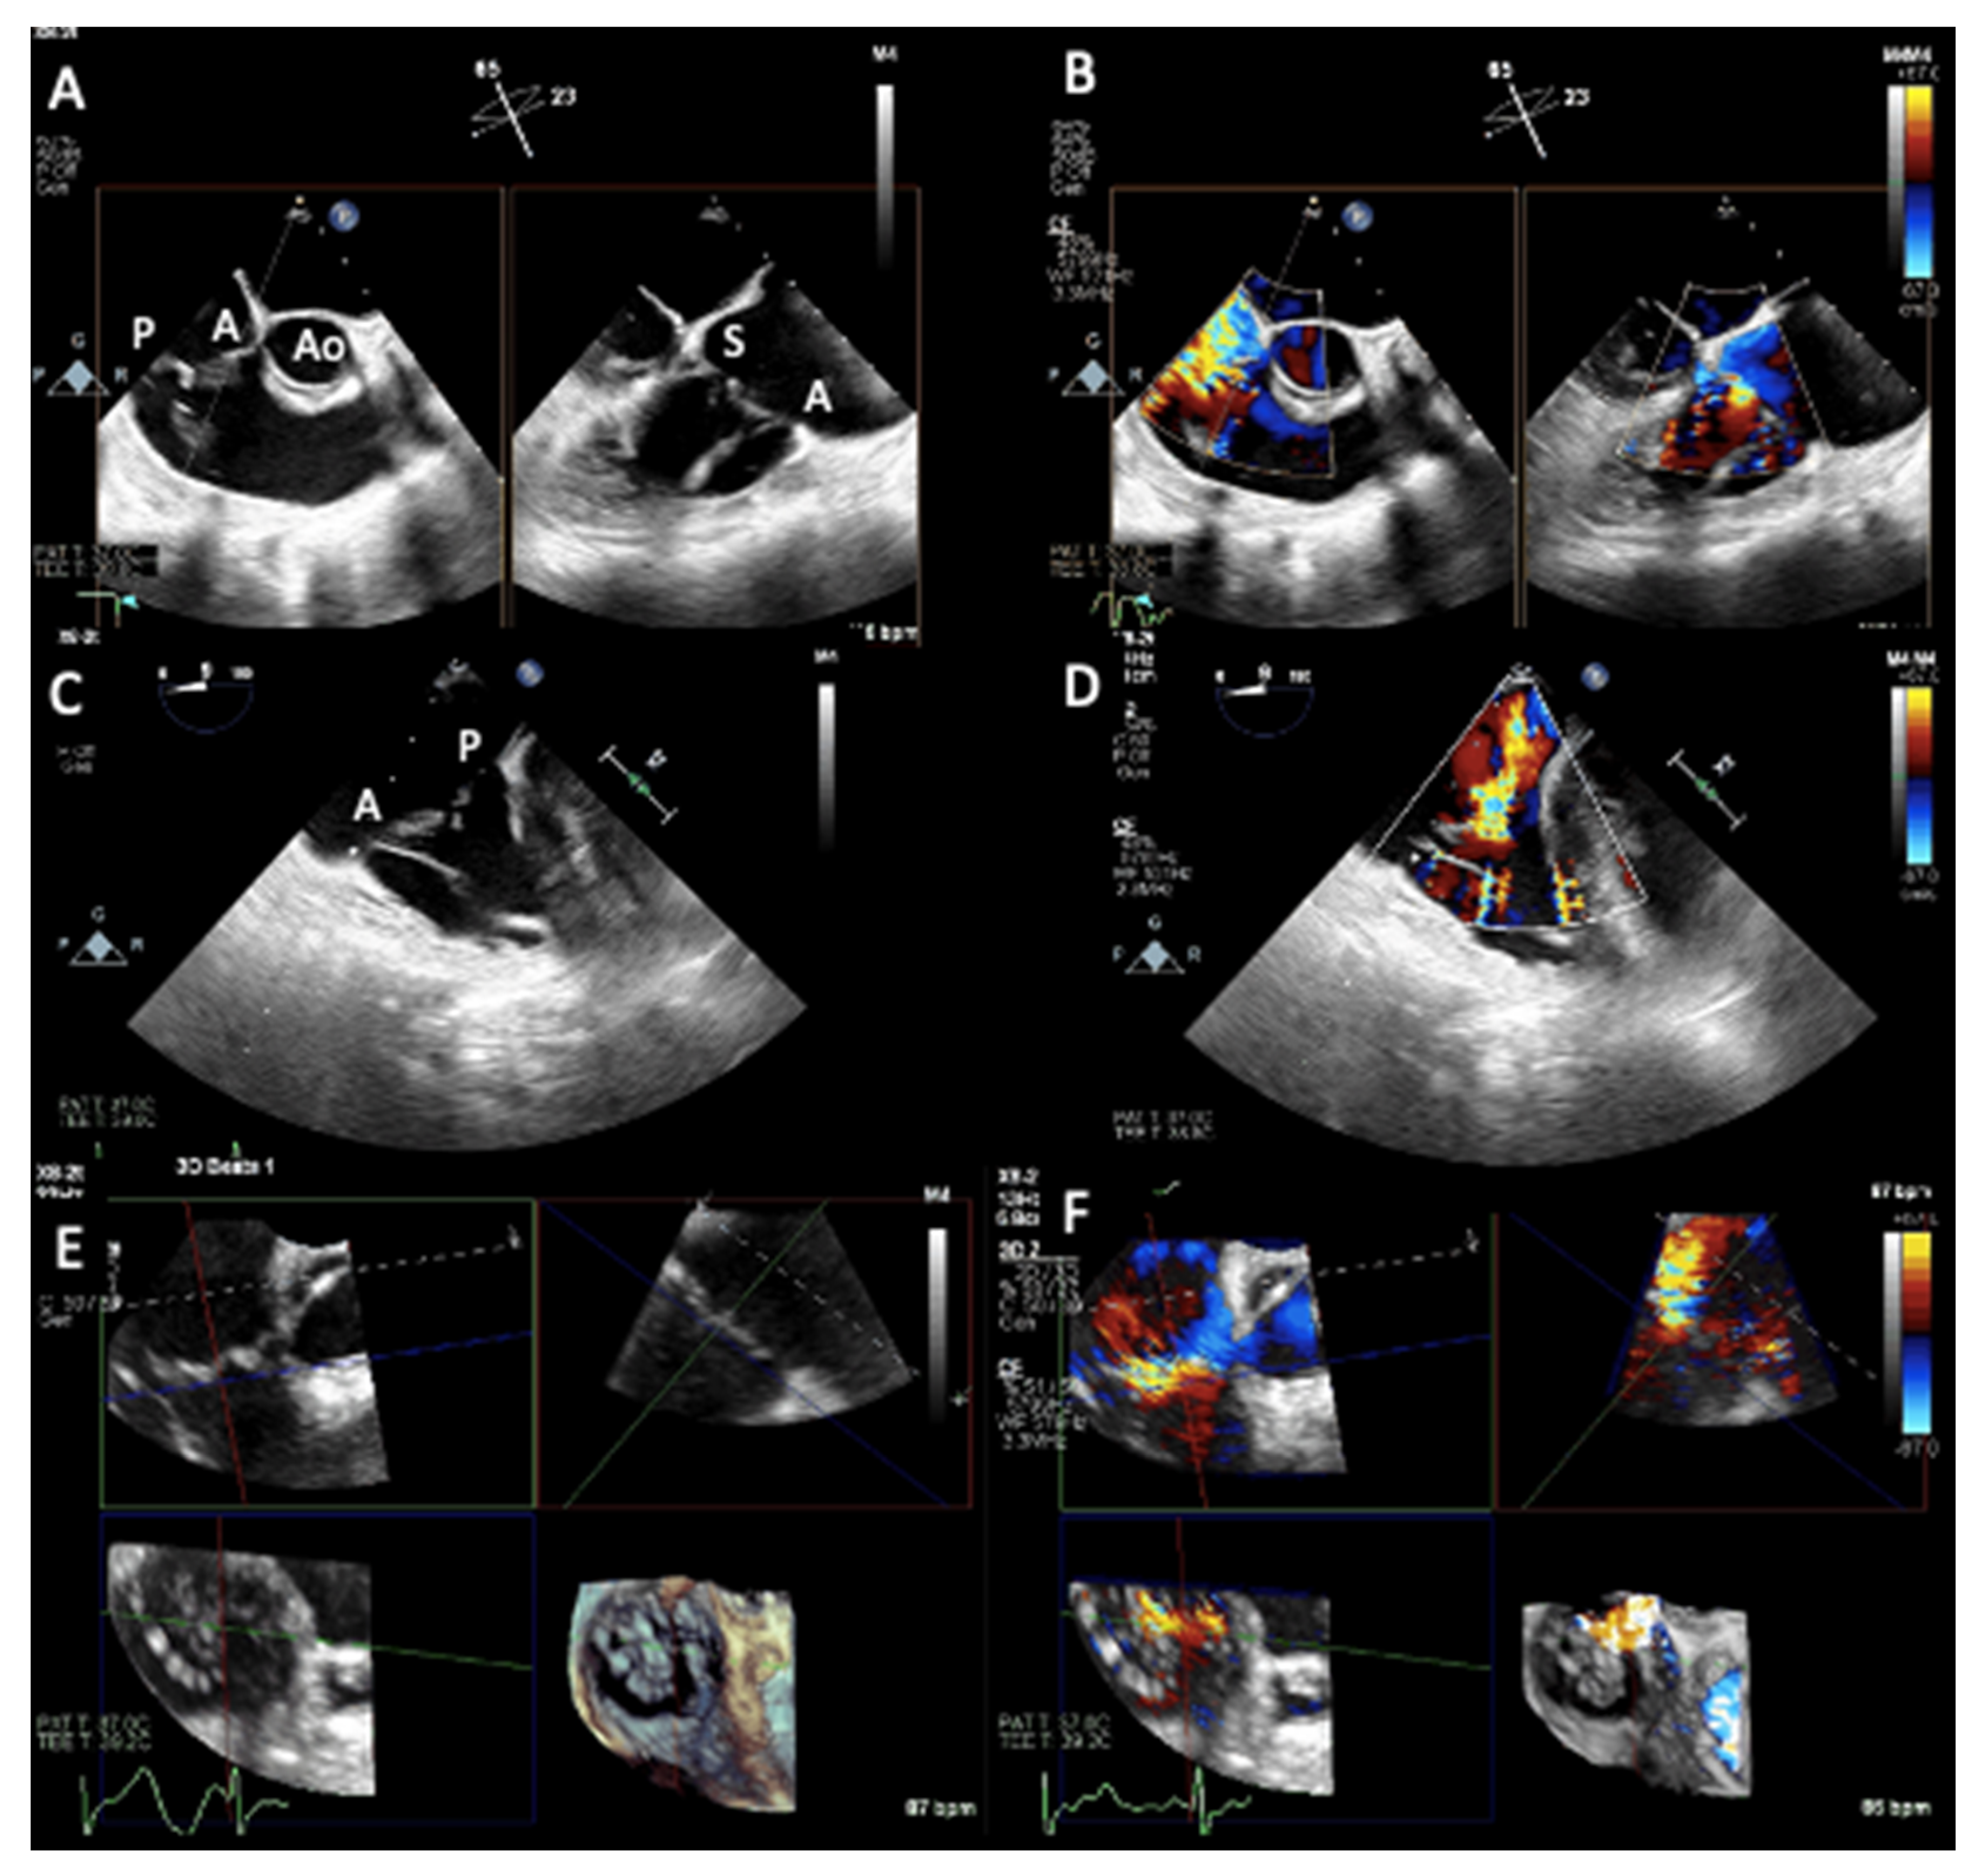

- Hahn, R.T.; Nabauer, M.; Zuber, M.; Nazif, T.M.; Hausleiter, J.; Taramasso, M.; Pozzoli, A.; George, I.; Kodali, S.; Bapat, V.; et al. Intraprocedural Imaging of Transcatheter Tricuspid Valve Interventions. JACC Cardiovasc. Imaging 2019, 12, 532–553. [Google Scholar] [CrossRef]

- Ro, R.; Tang, G.H.L.; Seetharam, K.; Khera, S.; Sharma, S.K.; Kini, A.S.; Lerakis, S. Echocardiographic Imaging for Transcatheter Tricuspid Edge-to-Edge Repair. J. Am. Heart Assoc. 2020, 9, e015682. [Google Scholar] [CrossRef] [PubMed]

- Agricola, E.; Ancona, F.; Stella, S.; Rosa, I.; Marini, C.; Spartera, M.; Denti, P.; Margonato, A.; Hahn, R.T.; Alfieri, O.; et al. Use of Echocardiography for Guiding Percutaneous Tricuspid Valve Procedures. JACC Cardiovasc. Imaging 2017, 10, 1194–1198. [Google Scholar] [CrossRef]